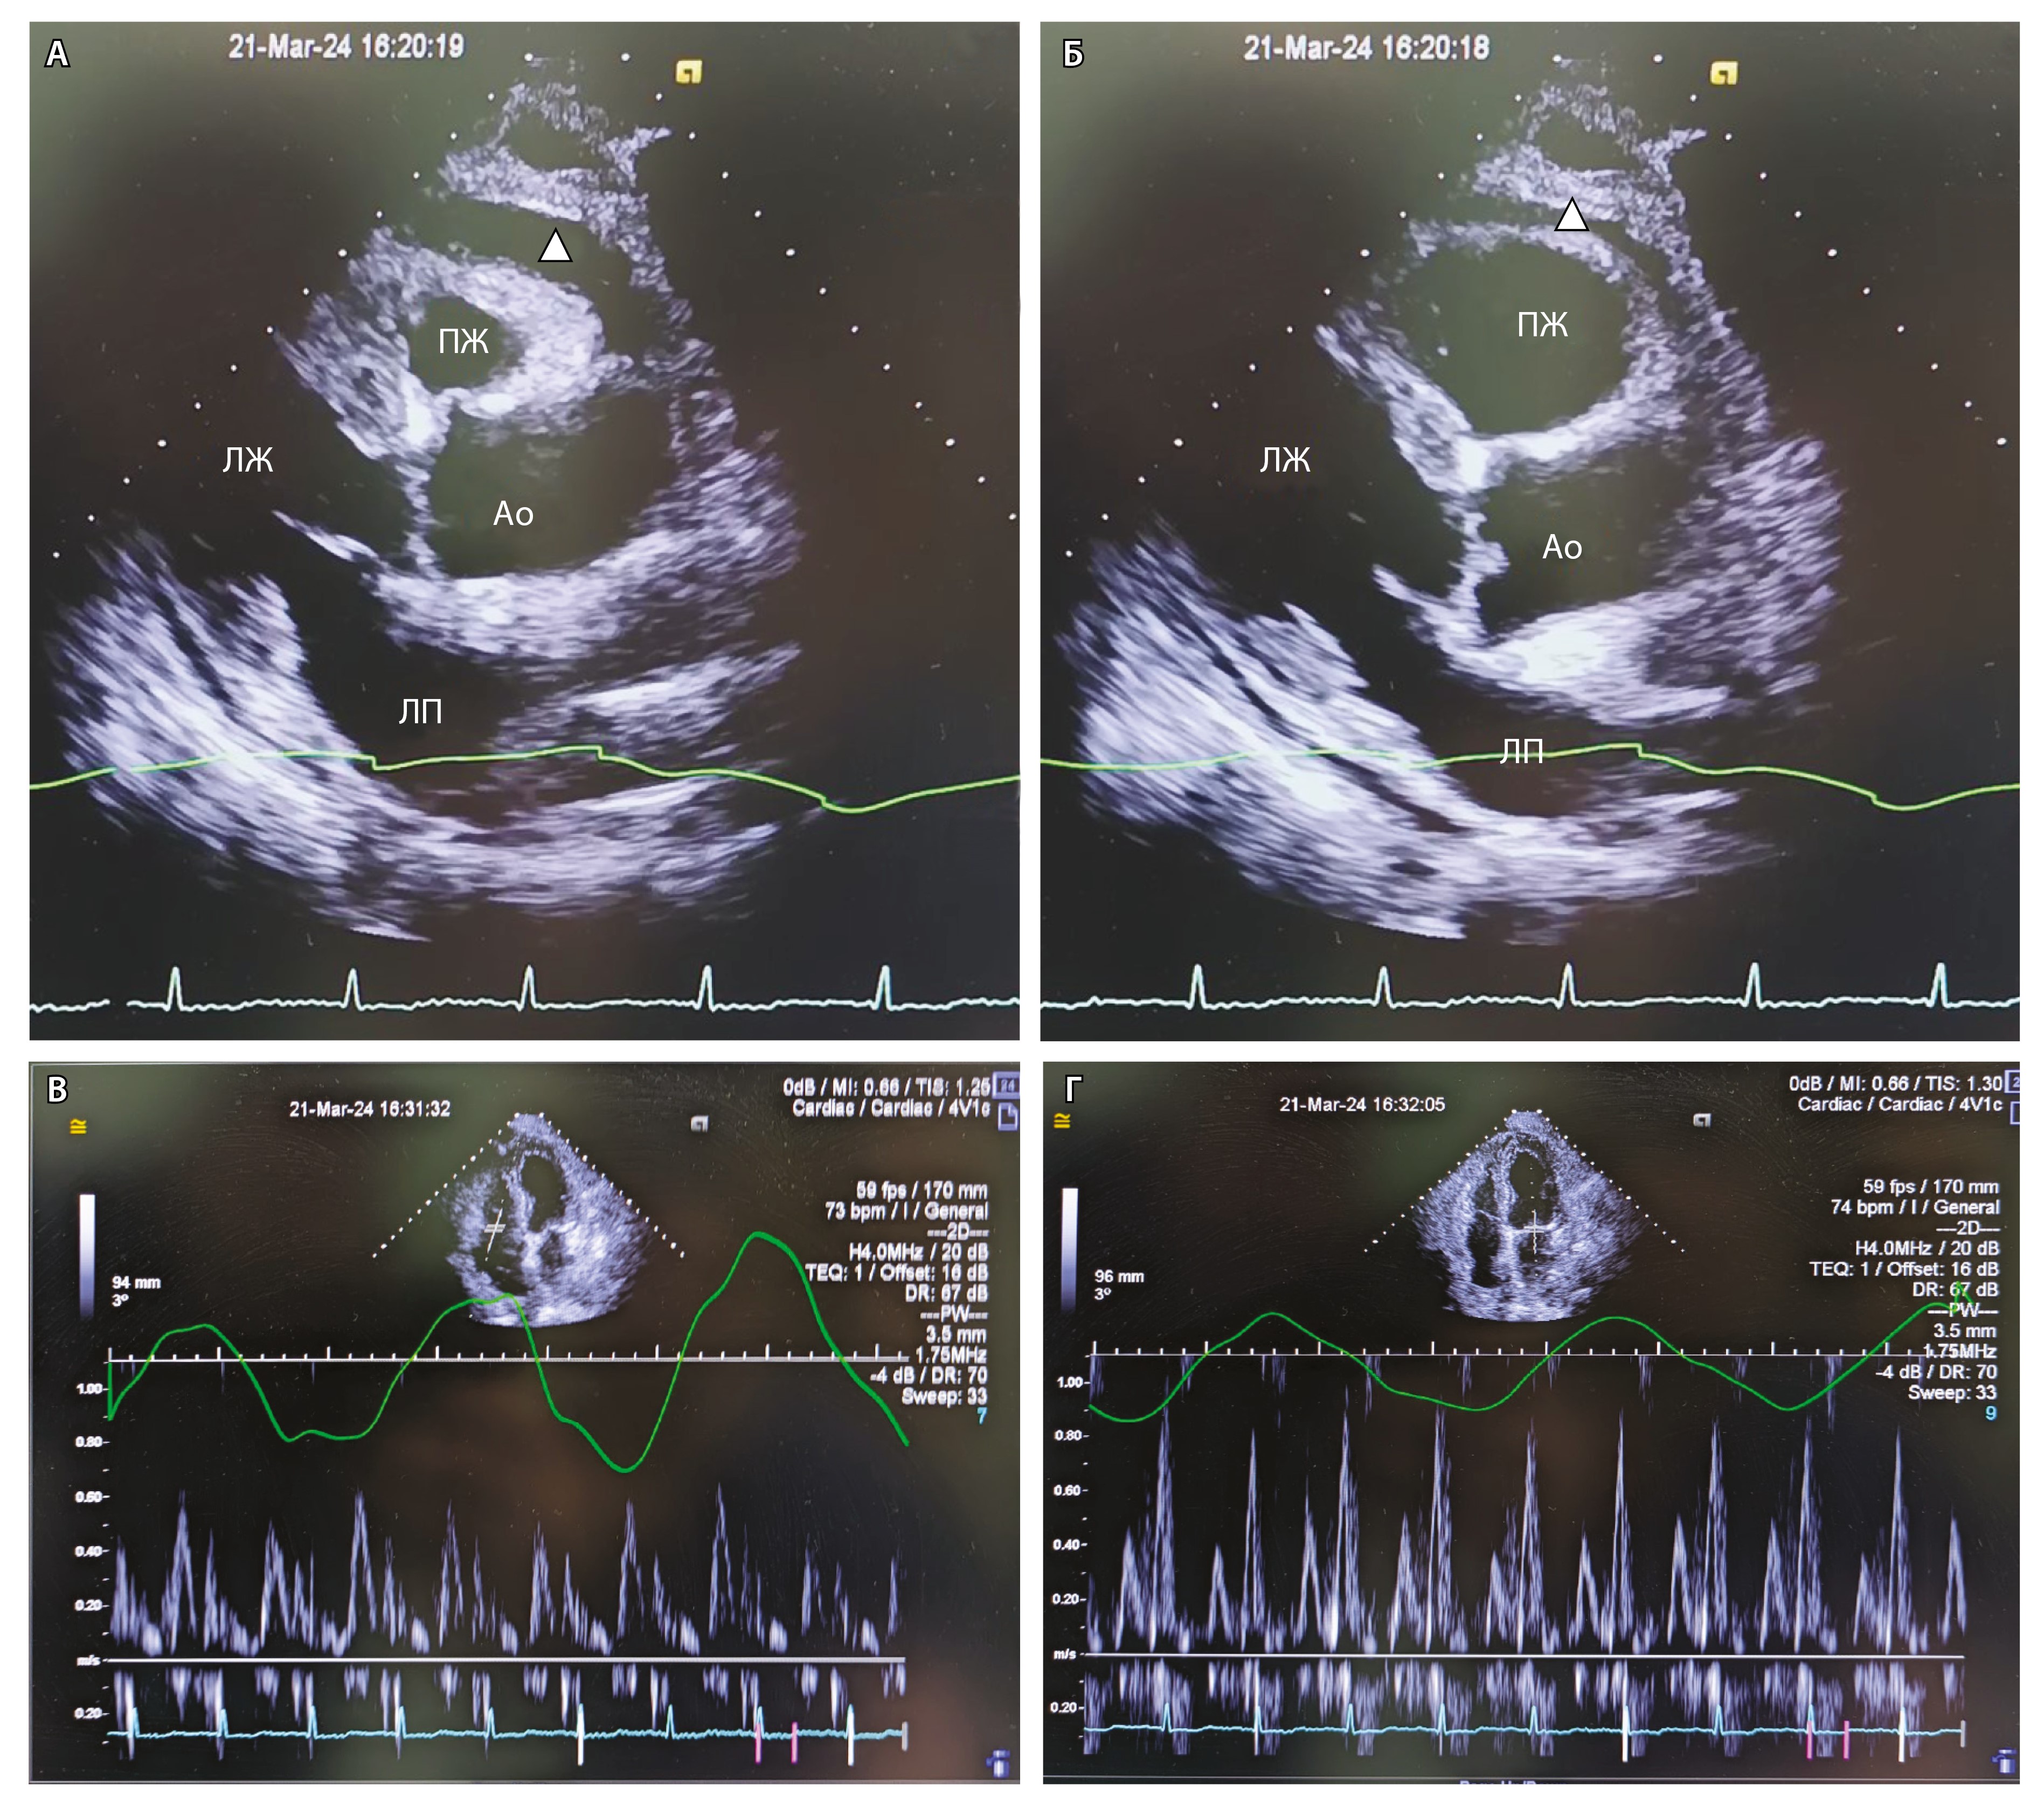

Повторно проведена Эхо-КГ (21.03.2024, рис. 3). По сравнению с предыдущим исследованием ФВ – 46%. Отмечается «дрожание» межжелудочковой перегородки. Отсутствует скользящее движение перикарда в области верхушки и боковой стенки ЛЖ. Количество жидкости в полости перикарда небольшое, без значимой динамики в сравнении с предыдущим исследованием: за задней стенкой ЛЖ – до 8 мм, над ПЖ – до 6 мм, диастолического коллапса ПЖ нет. При доплеровском исследовании – выраженное изменение скорости кровотока от фаз дыхания: на вдохе скорость трансмитрального кровотока снижается более чем на 25%, транстрикуспидальный кровоток повышается более чем на 25%. Выраженная дилатация НПВ – диаметр 34 мм, на вдохе не коллабирует. Диастолическая функция миокарда нарушена: E/A – 0,8, Elat – 10 см/с (N > 10 см/с), Emed – 8,7 см/с (N > 7 см/с), E'lat/E'med – 1,16 (N > 1,2, annulus reversus). Выявленные изменения свидетельствовали о том, что ведущим механизмом одышки и отеков у пациента была констрикция – ограничение подвижности миокарда выпотом и ригидным перикардом [14].

Рис. 3. Эхокардиограмма пациента: А – парастернальная позиция, длинная ось ЛЖ, систола; Б – парастернальная позиция, длинная ось ЛЖ, диастола; В – доплеровское исследование транстрикуспидального кровотока; Г – доплеровское исследование трансмитрального кровотока. Ао – аорта, ЛЖ – левый желудочек, ЛП – левое предсердие, ПЖ – правый желудочек. Белый треугольник указывает прослойку жидкости в перикарде